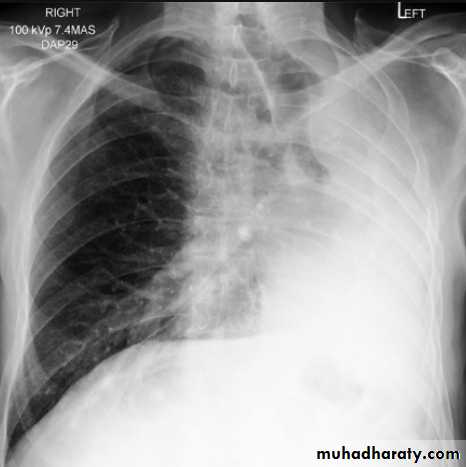

Right upper lobe collapse has distinctive features, and is usually easily identified on frontal chest radiographs .

Radiographic features

Chest radiograph

Collapse of the right upper lobe is usually relatively easy to identify on frontal radiographs. Features consist of :

increased density in the upper medial aspect of the right hemithorax

elevation of the horizontal fissure

loss of the normal right medial cardiomediastinal contour

elevation of the right hilum

hyperinflation of the right middle and lower lobe result in increased translucency of the mid and lower parts of the right lung

right juxtaphrenic peak

A common cause of lobar collapse is a hilar mass. When a right hilar mass is combined with collapse of the right upper lobe, the result is an S shape to elevated horizontal fissure. This is known as Golden S sign .

Non-specific signs indicating right sided atelectasis are also usually present including:

elevation of the hemidiaphragm

crowding of the right sided ribs

shift of the mediastinum and trachea to the right